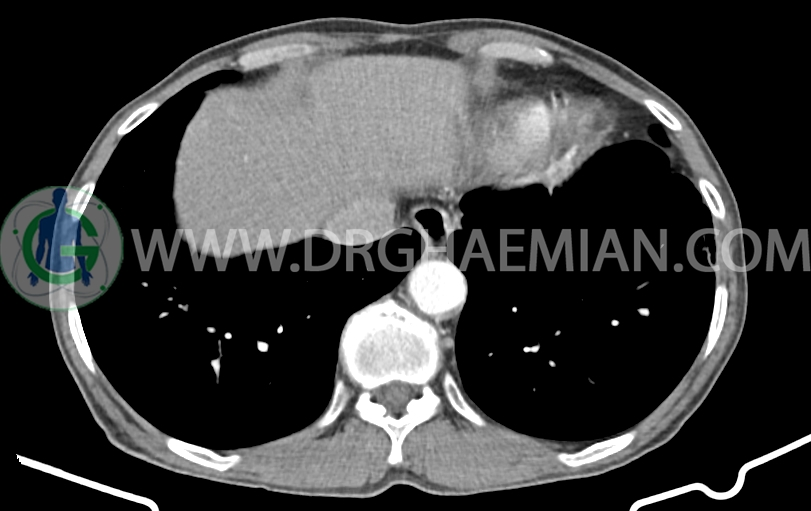

در سی تی اسکن اسپیرال ریه، مدیاستن و شکم و لگن با کنتراست خوراکی و وریدی (مولتی دیدکتور 16 با مقاطع ظریف و بازسازی های ساژیتال و کرونال) و مقایسه با سی تی اسکن 1401/06/06:

شواهدی استرنوتومی و کاردیومگالی خفیف

ژنیکوماستی خفیف دو طرفه